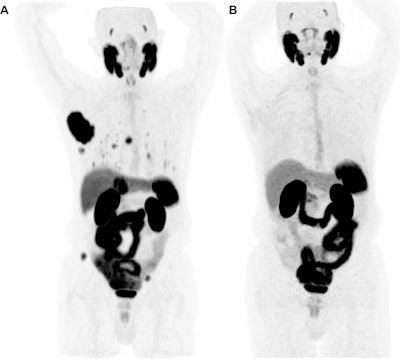

Complete response to immune checkpoint inhibitor therapy on Ga-68 PSMA-PET/CT. Maximum intensity projection (MIP) images from an 83-year-old male with metastatic HCC treated with atezolizumab and bevacizumab. (A) Baseline pretreatment image demonstrates a large, intensely PSMA-avid lesion in the right hepatic lobe, along with multiple metastatic lesions throughout the abdomen and skeleton. (B) Follow-up scan performed four months after initiating therapy shows complete resolution of PSMA uptake in all hepatic and extrahepatic disease.European Journal of Nuclear Medicine and Molecular Imaging